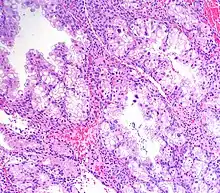

Micrograph showing Arias-Stella reaction in endometrium

Arias-Stella reaction, also Arias-Stella phenomenon, is a benign change in the endometrium associated with the presence of chorionic tissue.[1]

It is characterized by nuclear enlargement and may also have any of the following: an irregular nuclear membrane, granular chromatin, centronuclear vacuolization, and pseudonuclear inclusions.[1]